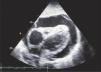

Apical 4 cámaras.Puede ser obtenido ubicando el transductor en el punto del latido de la punta del corazón y con el indicador hacia la izquierda. (Figura 8 y 9).